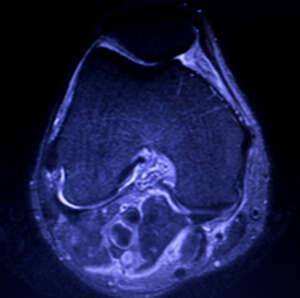

Als Meniskusriss oder Meniskusruptur bezeichnet man einen Riss eines oder beider Menisken des Kniegelenks. Innenmeniskusverletzungen (also des Meniscus medialis) sind wesentlich häufiger als die des Außenmeniskus (Meniscus lateralis). Die Risse werden nach ihrer Verlaufsrichtung in Längsriss, Radiärriss und Schrägriss (Lappenriss) eingeteilt. Bezüglich der Raumebene unterscheidet man Vertikalrisse und Horizontalrisse. Sonderformen sind komplexe Risse, der Korbhenkelriss und ein „flipped meniscus“. Eine weitere Sonderform des Meniskusrisses betrifft den anatomisch und therapeutisch besonders zu behandelnden Scheibenmeniskus. Die Diagnose erfolgt durch klinische Untersuchung, Kernspintomographie und Arthroskopie (Gelenkspiegelung). Meniskusrisse sind recht häufig und oft bestehen keine Schmerzen oder Einschränkungen. Nicht jeder Meniskusriss muss behandelt werden.

Vor einer Operation muss die Diagnose meist durch eine MRT bestätigt werden. Dann erfolgt bei älteren Menschen mit geringem sportlichen Anspruch meist eine teilweise Resektion der gerissenen Meniskusanteile mittels Kniegelenks-Arthroskopie (Gelenkspiegelung). Besonders bei Kindern und Jugendlichen haben die Menisken eine zentrale Aufgabe bei der Kniegelenksfunktion und bei deren langfristigem Erhalt. Daher sollten bei Kinder, Jugendlichen und sportaktiven Erwachsenen Meniskusrisse am besten operativ, d. h. arthroskopisch mit einer Naht behandelt werden, um so wenig Meniskusgewebe wie möglich zu opfern.